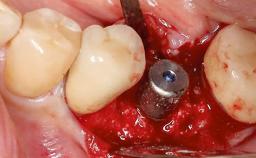

In this case, Nicola Zitzmann describes the sudden loss of a previously well-osseointegrated implant that had been in healthy function for 5 years. The case includes recommendations for occlusion and function of implant restorations. A 74-year-old patient had received implant-fixed dental prostheses in the maxilla in 2008, and in the right mandible three years later. His tooth loss was mainly related to recurrent caries associated with hyposalivation as a potential side effect of his cholesterol-lowering medication.